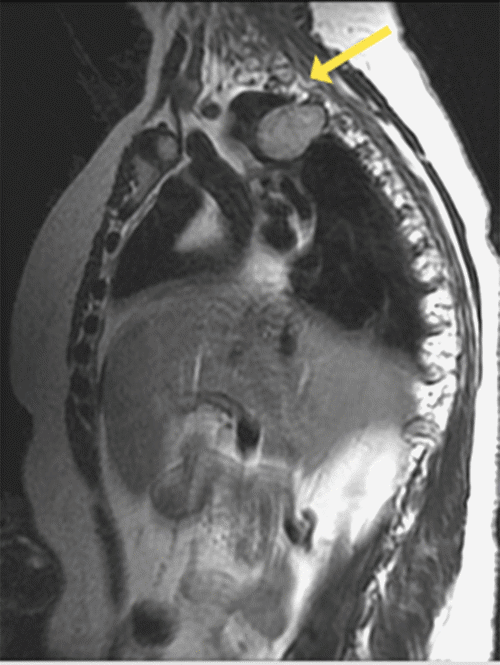

Figure 1. MRI: Axial T2-Weighted Image. Published with Permission

A. Thoracic spine at the level of T2, demonstrating right-sided mass extending out of the T2 neural foramen (arrow) and into the thoracic cavity.

B. Sagittal T2 image shows the mass extending into the right hemithorax (inferior to arrow).

A 67-year-old woman was incidentally found to have an asymptomatic thoracic paraspinal tumor. Magnetic resonance imaging (MRI) of the thoracic spine performed for an unrelated work injury showed an extradural, lobulated mass originating in the right neural foramen of T2, with extension into the right pleural cavity and posterior mediastinum. The mass measured 5.2 × 4.7 × 3.6 cm, and a mild mass effect was seen on the right posterior trachea and adjacent lung. However, it was also well-circumscribed and homogenously enhancing with no evidence of associated osseous destruction or mass effect on the spinal cord, suggestive of a benign peripheral nerve sheath tumor (PNST [Figure 1]). Given that her asymptomatic and benign pathology was suggested by imaging, the patient elected for conservative management with routine surveillance.